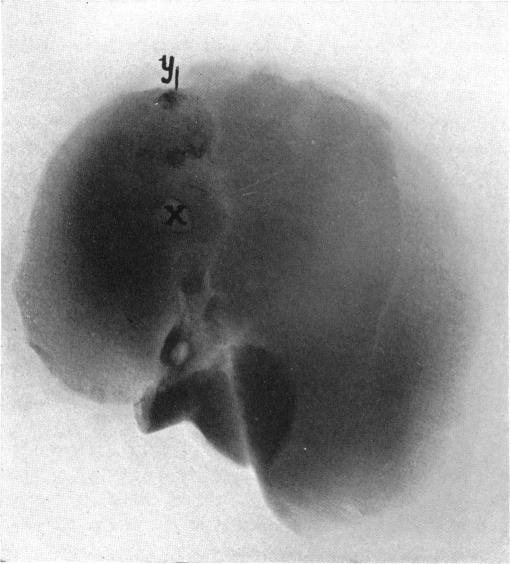

CALCIUM CARBONATE GALL-STONES AND THEIR EXPERIMENTAL PRODUCTION.

Ann Surg. 1932 Oct;96(4):595-614. doi: 10.1097/00000658-193210000-00011.